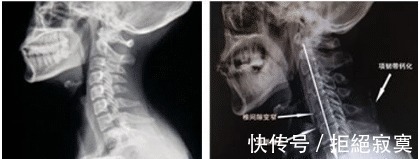

颈椎病反复不好,一样小物就能解决,身边有颈椎病的可以保存了大家好呀,我是养生博主小智。很多人现在都很注重养生了,身体健康是做任何事情的前提,所以每天就由小编带大家进入养生小课堂吧。颈椎病又称颈椎综合征,是颈椎骨关节炎、增生性颈椎炎、颈神经根综合征、颈椎间盘脱出症的总称,是一种以退行性病理改变为基础的疾患。

主要由于颈椎长期劳损、骨质增生,或椎间盘脱出、韧带增厚,致使颈椎脊髓、神经根或椎动脉受压,出现一系列功能障碍的临床综合征。表现为椎节失稳、松动;髓核突出或脱出;骨刺形成;韧带肥厚和继发的椎管狭窄等,刺激或压迫了邻近的神经根、脊髓、椎动脉及颈部交感神经等组织,引起一系列症状和体征。